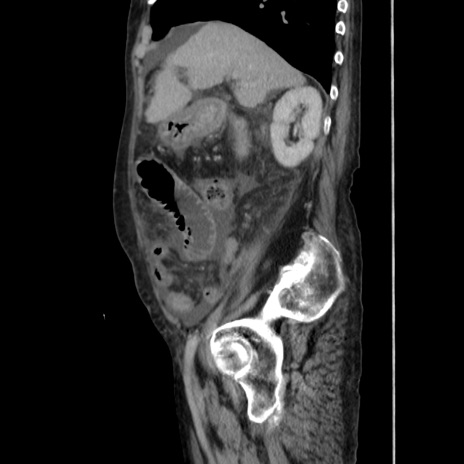

症例31(矢状断像)

【症例】80歳代 女性

【主訴】腹部膨満感

【現病歴】他院にて肝硬変にてフォロー中。1週間前から便秘、腹部膨満感、臍部腫瘤あり受診となる。

【既往歴】肝硬変

【身体所見】腹部膨隆あり、皮膚変化なし、疼痛なし。

【データ】WBC 4600、CRP 0.25